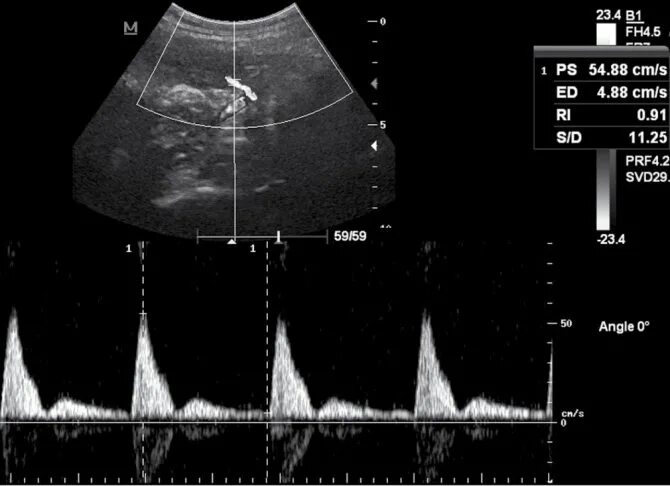

Допплерометрия маточных